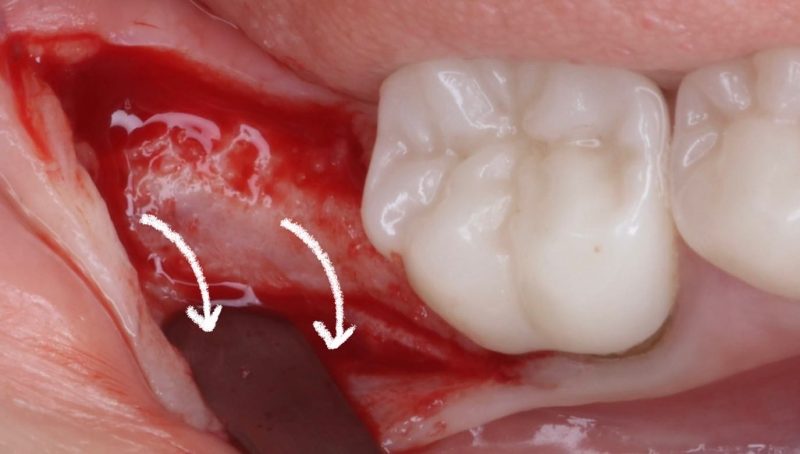

When dealing with these cases, I intentionally make my incision more lingual to preserve as much tissue as possible for the buccal side. I place the implant 1.5mm subcrestal to ensure proper stability and room for bone and soft tissue regeneration. Once the implant is in place, I use a healing cap and reposition the tissue, which allows us to achieve a thick, healthy band of keratinized tissue on the buccal.